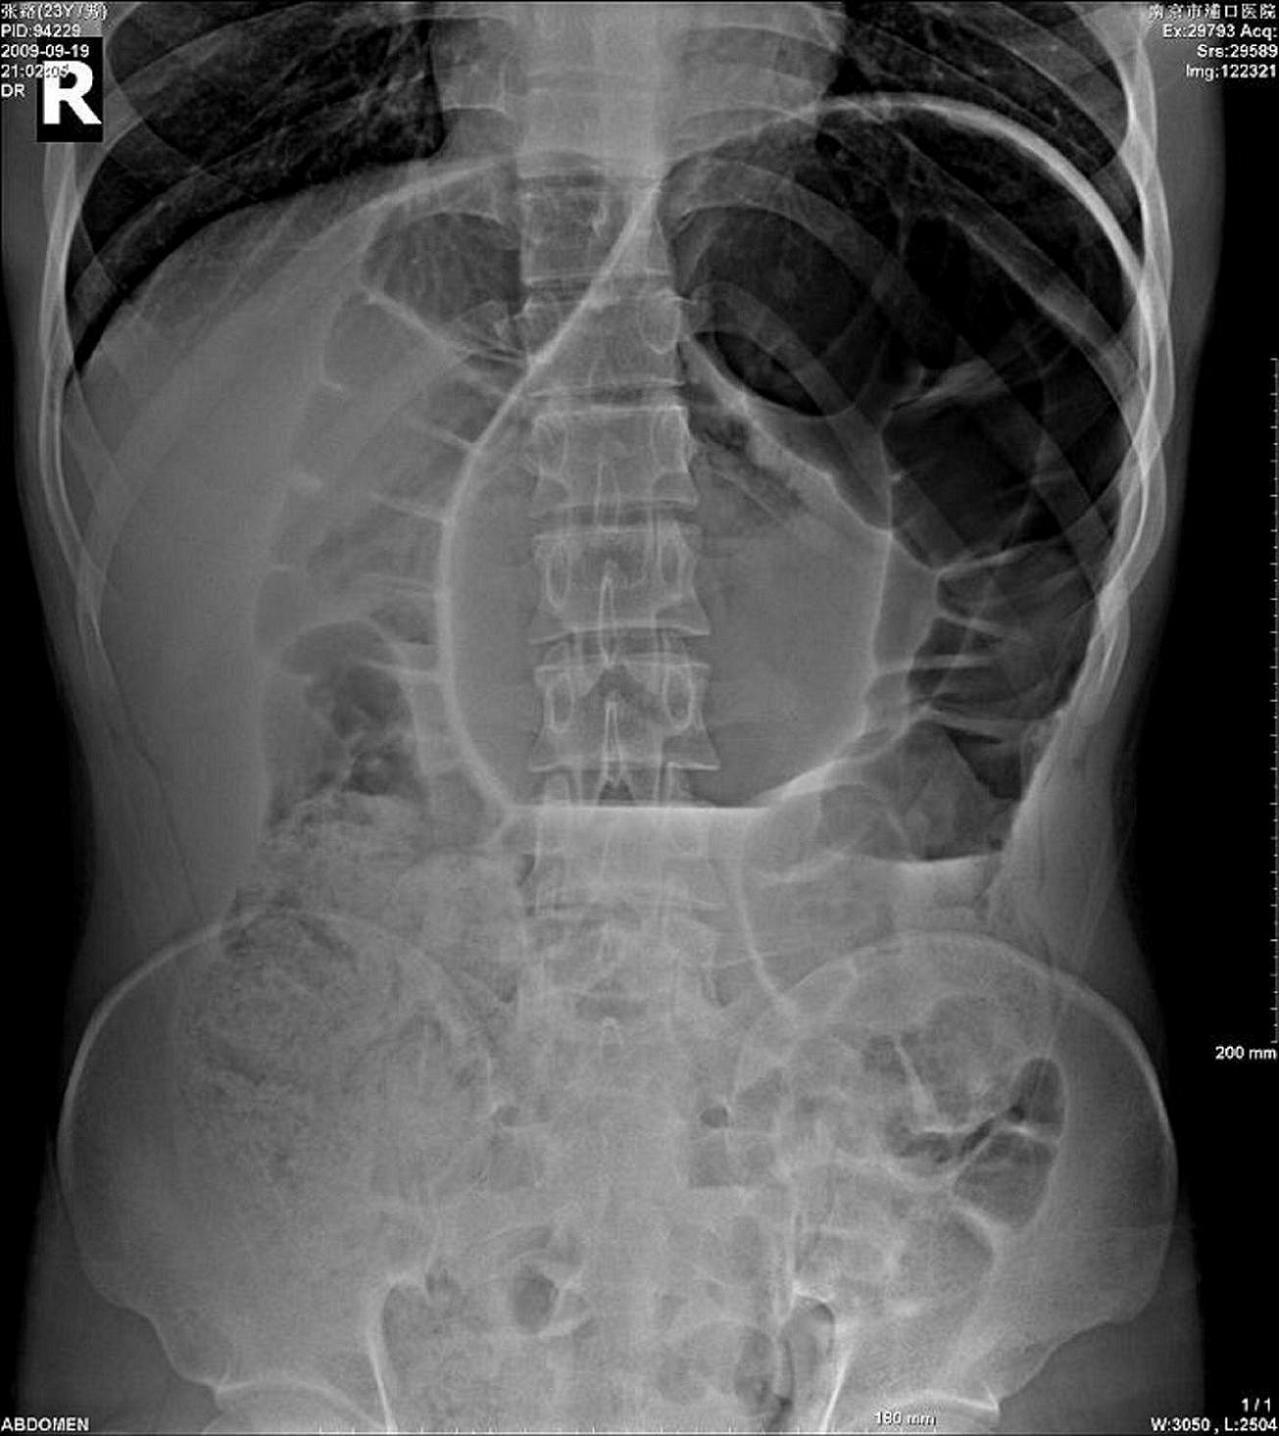

男性,23岁,急性腹痛12小时,来院检查,腹胀明显,拍胸、腹片如图示:

我觉得是典型的咖啡豆征,应该是肠扭转。

肠管明显扩张伴长液平面,以结肠为主,考虑肠扭转引发梗阻可能,位置较高不太像乙状结肠。

单个胀大的双袢肠曲自盆腔延至膈下,结合临床急腹症病史,首先考虑乙状结肠扭转;建议结合钡灌肠检查。